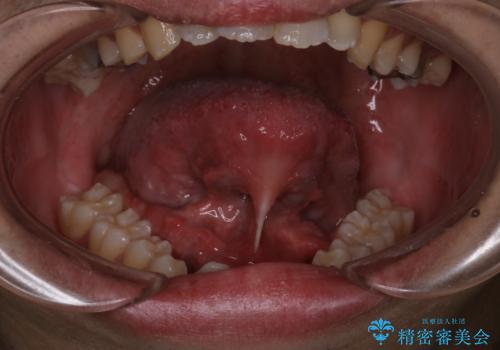

[ 舌小帯の形成術 ] 「ら行」や「た行」が発音しづらいのを改善したい!

担当医 大元洋佑

![[ 舌小帯の形成術 ] 「ら行」や「た行」が発音しづらいのを改善したい!の症例 治療前](https://seimitsushinbi.jp/wp/wp-content/uploads/2023/12/7d9ac5f7c2f3679a481af9859a64f532-500x350.jpg?v=1701830486)

![[ 舌小帯の形成術 ] 「ら行」や「た行」が発音しづらいのを改善したい!の症例 治療後](https://seimitsushinbi.jp/wp/wp-content/uploads/2023/12/999705bbf9ee513b86dbb3839372e65b-500x350.jpg?v=1701830502)